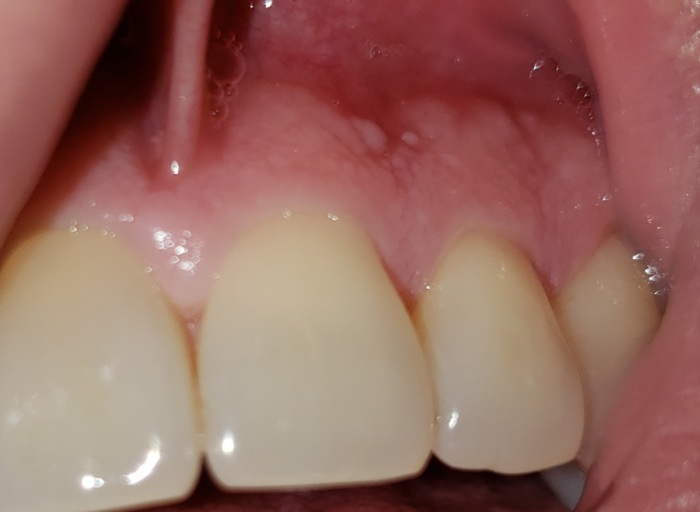

I had a tooth pulled and I got dry socket now I have a lump that seems to have a head on it.. I am taking antibiotics clindamycin 300mgx3daily. The pain is gone in my jaw but the lump is sensitive.I go back to my dentist saturday. But I am so worried about this now. Is there any way to so you a picture? I am alergic to penicillin and. I have dental anxiety. I just want to know if it is an abscest. It has not grown any but it also has not srunck. But my tongue it feels about the size of a marble. Can you get an abscest from dry socket?

The picture submitted appears to be the tissue healing. It can be sore, tender, and swollen during this process. It is hard to see if there is a suture, however as long as you are keeping it clean, free of debris, and taking your antibiotics as directed, you are doing everything you can to avoid an infection. The pain subsiding is a good indication that the area is healing. Continue to be cautious until you have had clearance from the surgeon to resume regular activity and resume a normal diet. Having an abscess form after the tooth removed is possible, but not likely if you are following your post operative care instructions and taking your antibiotics as directed.